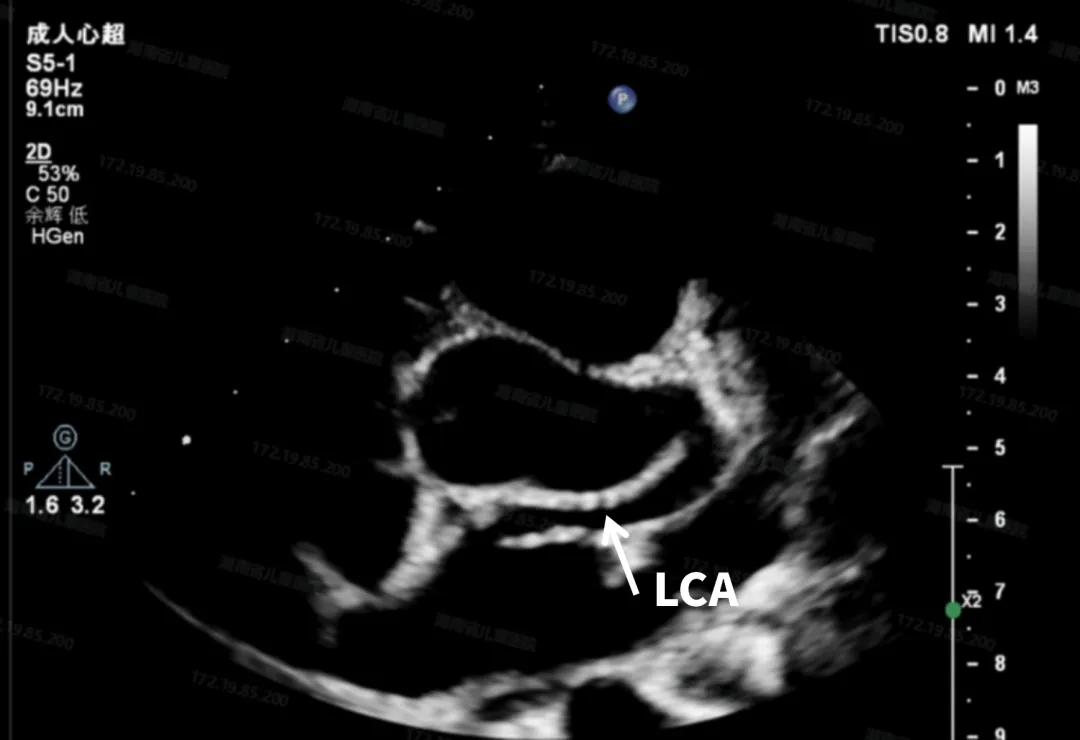

术前超声检查

超声下可见左冠状动脉异常增宽

左回旋支向右发出一支血管前走行汇入右心房